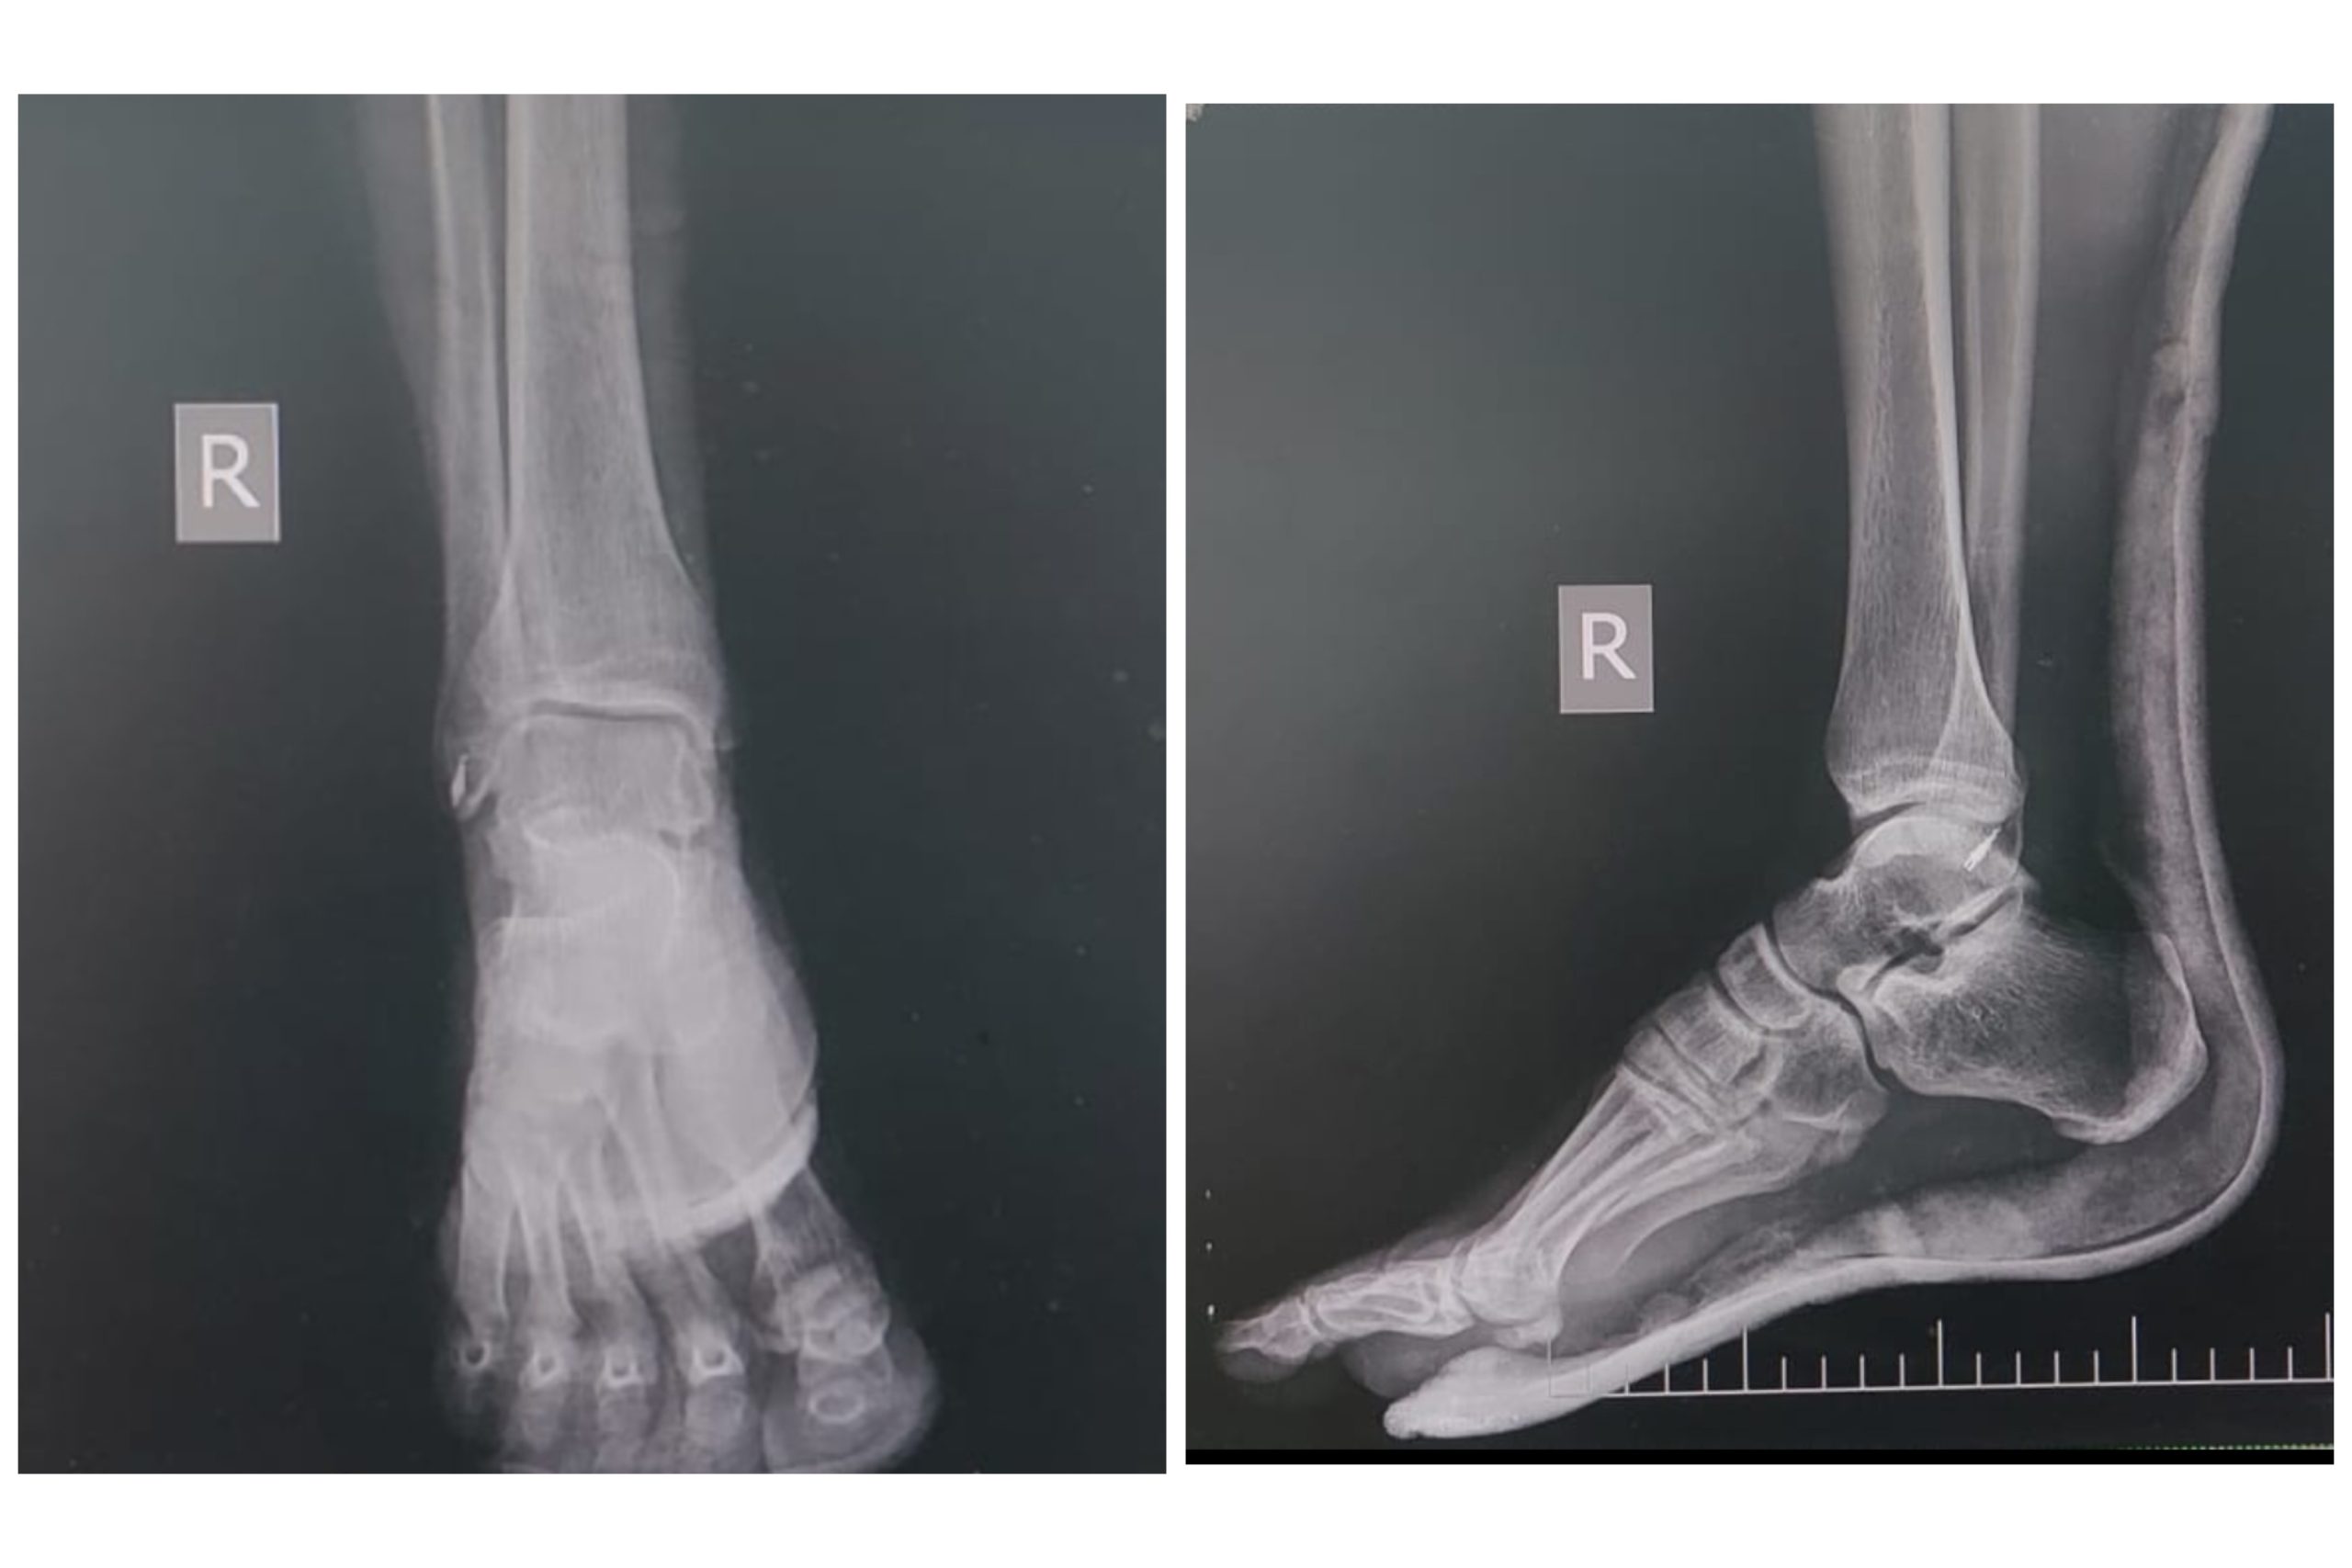

Расположение сухожилий в области стопы и голеностопа

Обратите внимание‚ что сухожилия малоберцовых мышц проходят через достаточно узкие каналы‚ образованные костью и связками. В области лодыжки они проходят над латеральным малоберцовым бугром‚ а затем направляются к костям стопы. Благодаря такому пути они обеспечивают контроль за движениями и стабильностью при нагрузках.